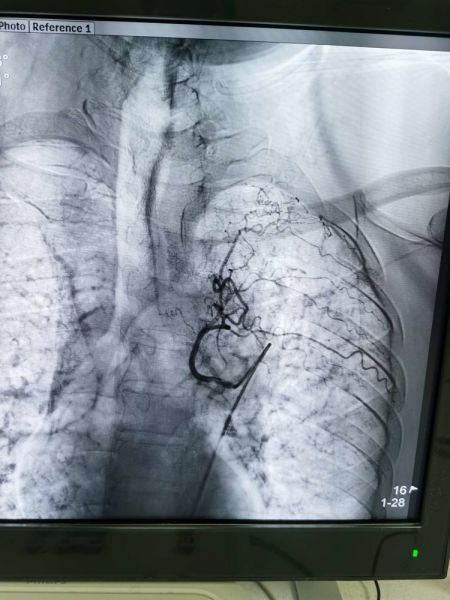

杨某反复咯血十余天,于元月23日住院,入院诊断:肺炎并咯血,结核?高血压病,二型糖尿病。大年三十下午三点三十分急诊手术,DSA示:右上支气管动脉发现多个出血灶。

栓塞后病灶出血停止

左下支气管动脉发现多个出血灶

左上支气管动脉与出血病灶动脉交通

用栓塞微粒球+PVA+弹簧圈三明治方法栓塞满意,手术历时一小时四十分钟,共栓塞三支犯罪血管,元月31日康复出院。